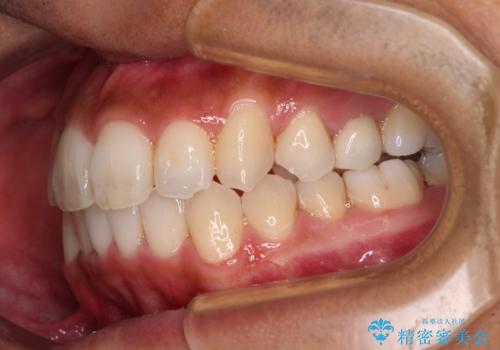

- 前歯のデコボコとクロスバイトを気にして来院された患者様です。

下顎の歯列弓に対して上顎歯列弓がやや小さく、側方の歯を中心にクロスバイトが見受けられました。

クロスバイトの改善は、インビザラインの場合歯髄壊死のリスクや咬み合わせが改善しきらないリスクがあるため、ワイヤー矯正をお勧めすることが多いですが、患者様の希望によりインビザラインにて矯正治療を行うこととしました。

奥歯の咬み合わせは接触が少なく物足りないように見えますが、患者様としては十分に咬むことができるとのことでした。